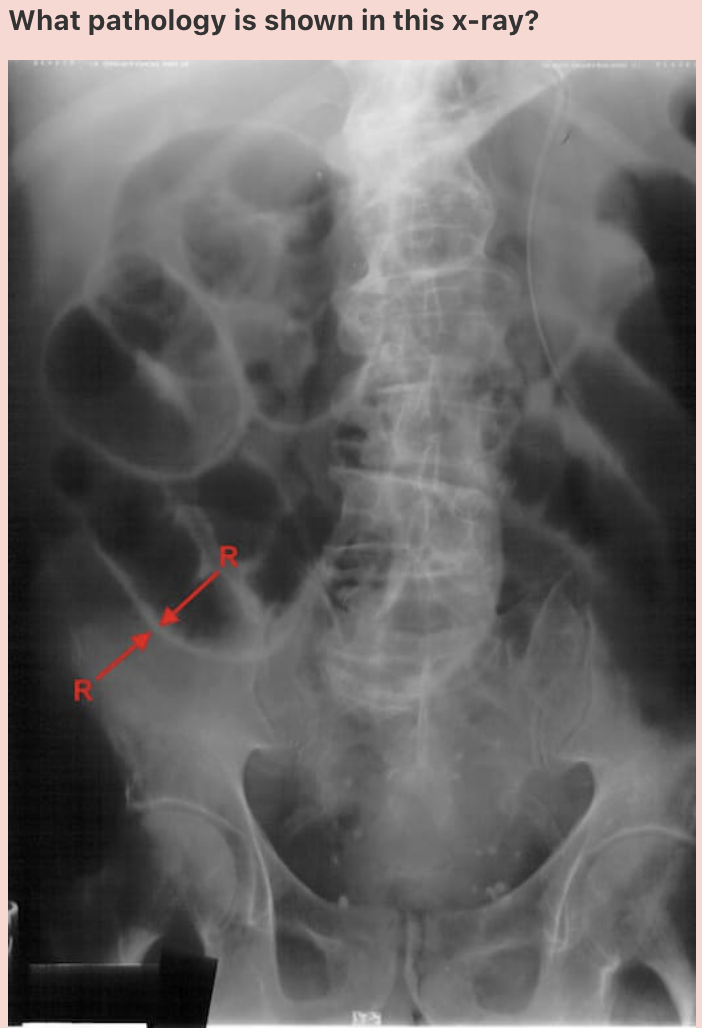

Answer: Ulcerative colitis

‘Lead pipe sign’ is noted in the descending colon, on the right border of this image.